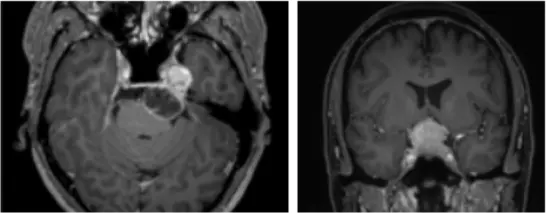

-일반 뇌 CT·MRI 검사를 통해 확인 가능한가?

“두개저를 자세히 볼 수 있는 CT검사가 필요하다. 종양이 침범한 위치를 파악하기 위해 MRI 검사도 실시한다. 종양이 시신경이나 청신경을 압박하고 있으면 시각 검사, 청각 검사와 같은 기능 검사를 하고, 양성·악성 여부 판별을 위한 PET 검사 또한 진행할 수 있다. 두개저종양 수술은 두개저를 통해 뇌로 향하는 주요 혈관들을 손상시키지 않는 것이 중요하기 때문에 두개저종양이 발견되면 우선 뇌혈관 조영술을 통해 혈관들을 확인한다.”